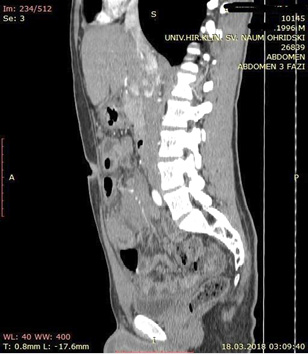

A contrast enhanced CT scan was indicated due to the palpable abdominal tumor and it revealed a formation that originates from the ileal mesentery involving the ileocolic artery and a part of the ileum with ileal wall thickening and partial obstruction (Figures 2, 3 and 4).

24.jpg Figure 2 23.jpg Figure 3

25.jpg Figure 4